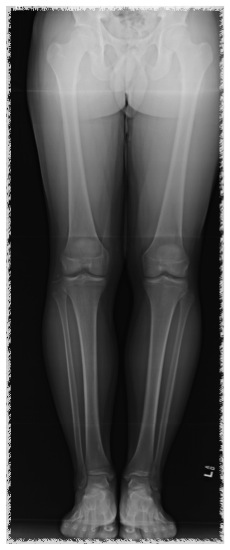

Long leg views

- assess for varus malalignment

Varus malalignment left knee

ACL + high tibial osteotomy